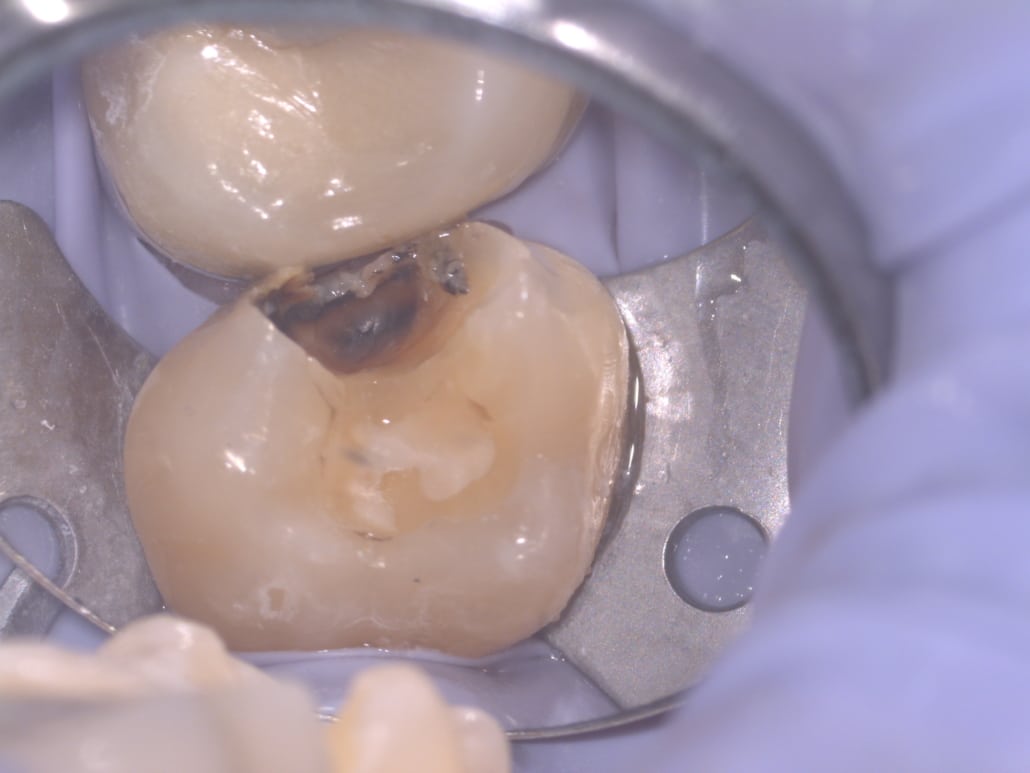

Exemples de caries vues par microscope

Exemple de fêlure constatée située sous un ancien plombage, qui provoquait des douleurs chez le patient. Un nettoyage et un composite ont été effectués.